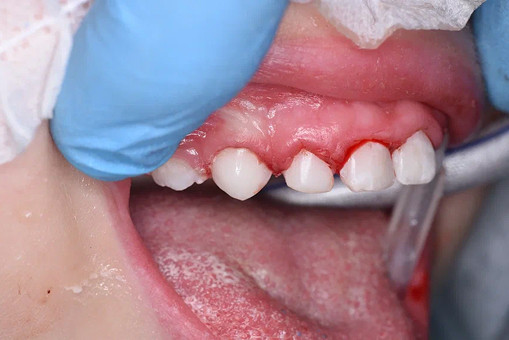

Лечение кариеса проводится следующим образом - сбор анамнеза, проведение местной анестезии, дентальный снимок (при необходимости), изоляция (коффердам), фотопротокол, удаление кариозных тканей (с использованием бора), антисептическая обработка полости, реставрация пломбировочным материалом, шлифовка, полировка.

До/после лечения